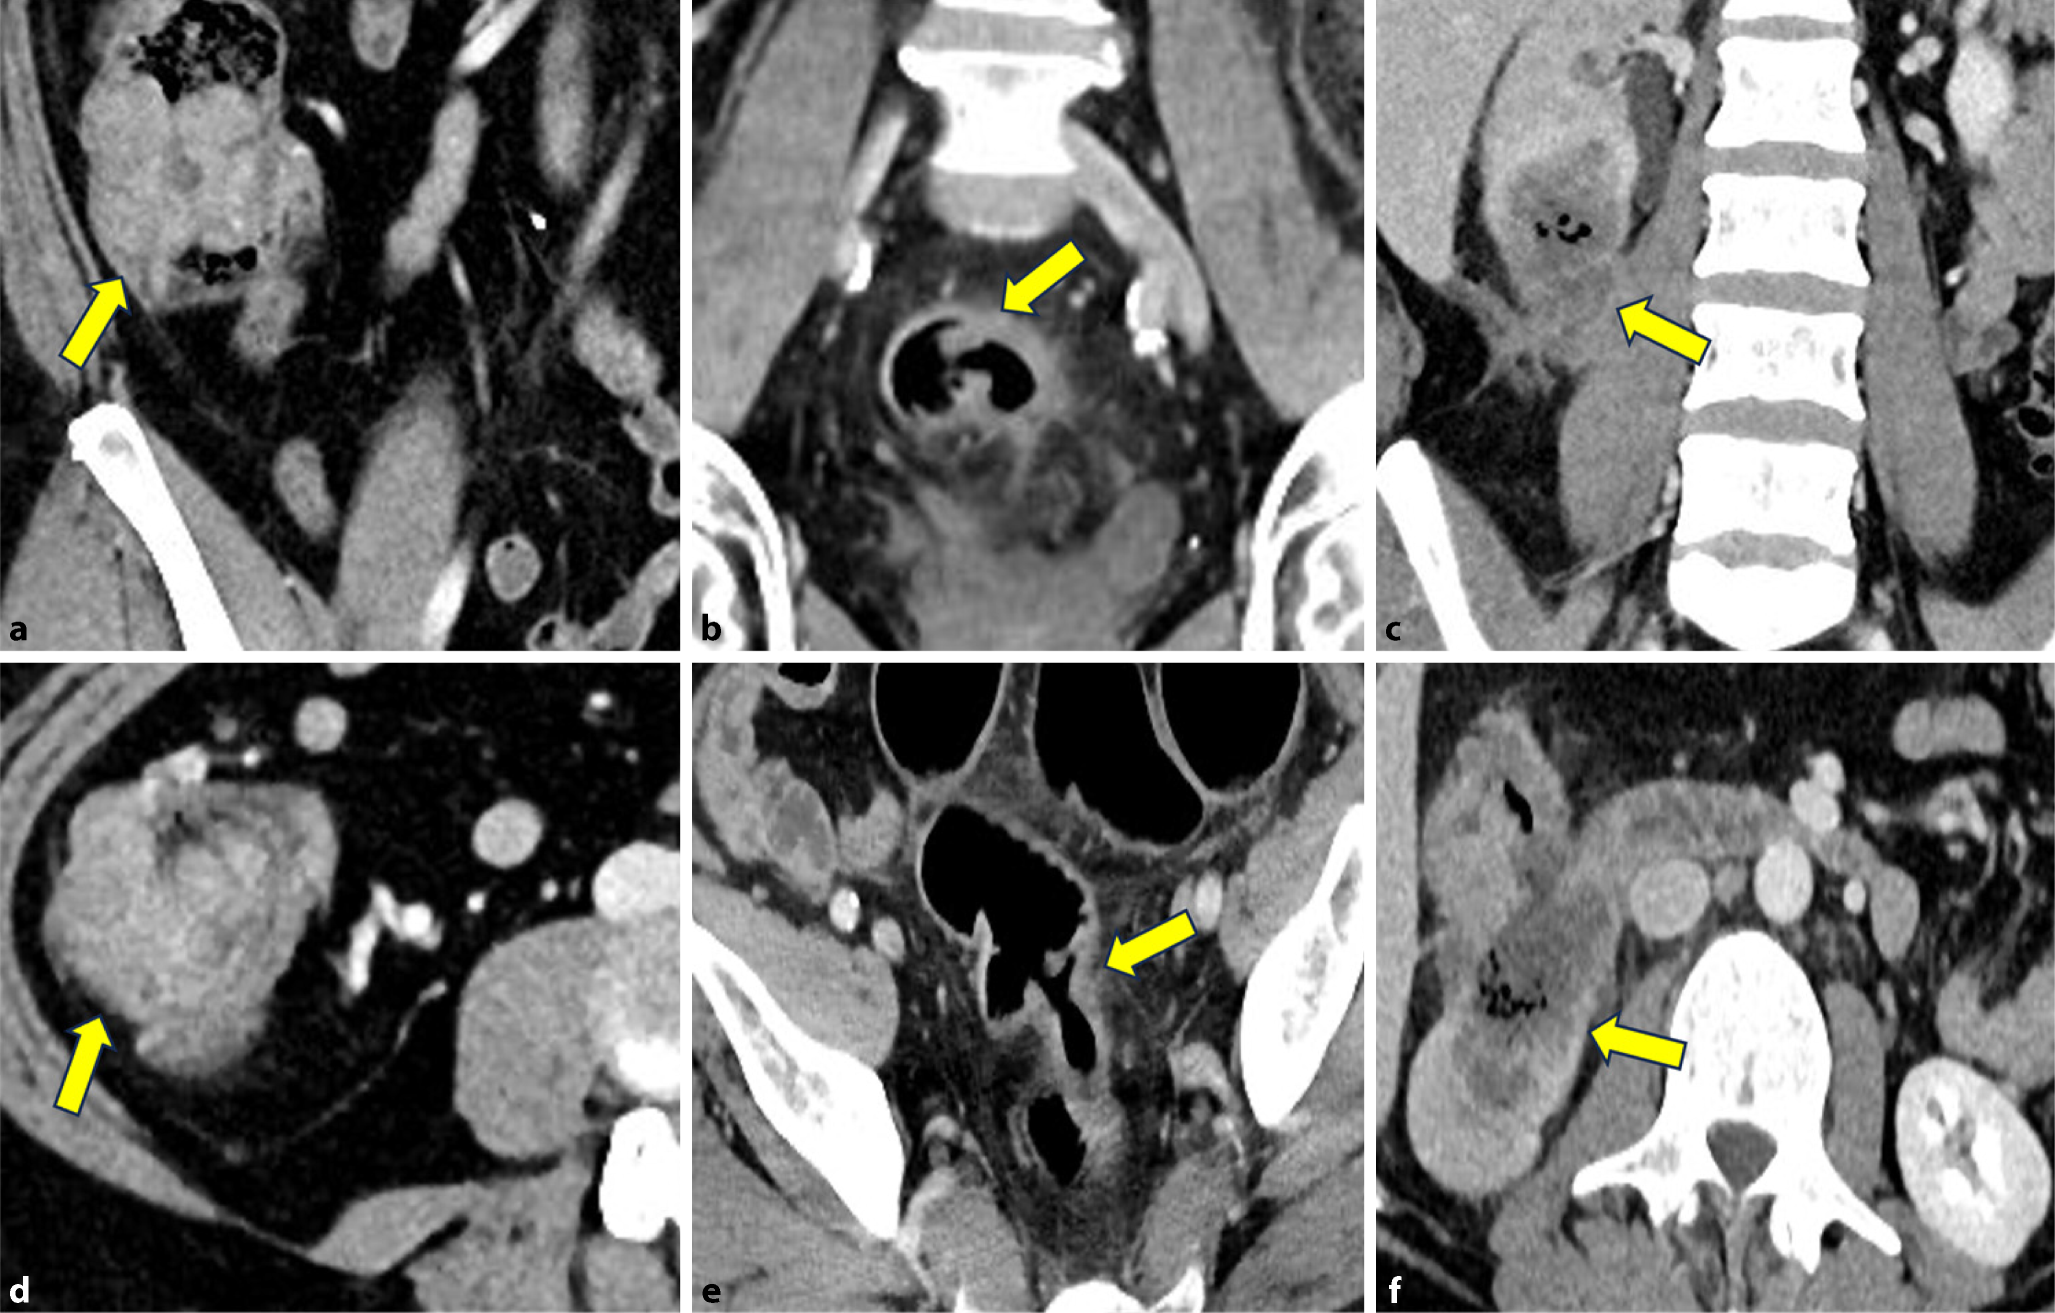

Kolonkarzinome können sich entweder als polypoide Raumforderungen oder als (semi-)zirkumferente, fokale Verdickungen der Wand darstellen. Abb. 1 zeigt die lokale Stadieneinteilung der Kolonkarzinome. Es muss allerdings beachtet werden, dass T1- bis T2-Stadien mittels CT schwer zu unterscheiden sind und daher auch zusammengefasst werden. T1/2-Tumoren überschreiten die Muscularis propria (Abb. 2a, d) nicht. T3-Tumoren können in T3ab und T3cd unterteilt werden. T3ab-Tumoren infiltrieren die Serosa und überschreiten sie bis max. 5 mm (Abb. 2b, e). T3cd-Tumoren überschreiten die Serosa um mehr als 5 mm. T4a-Tumoren infiltrieren das Peritoneum und T4b-Tumoren infiltrieren angrenzende Organe (Abb. 2c, f). In Tab. 1 sind die genauen Definitionen der einzelnen Unterkategorien angegeben.

Abb. 2

a–c Axial. d–e Koronal. a, d 56-jähriger Patient mit einem Karzinom im Zökum. Weder axial (a) noch koronal (d) zeigt sich eine Wandüberschreitung (T2 N0 M0, gelbe Pfeile). b, e 78-jähriger Patient mit einem Karzinom im Sigma. Vor allem auf der axialen Serie (b) zeigt sich eine deutliche Imbibierung des angrenzenden Fettgewebes (gelbe Pfeile) im Sinne einer Infiltration (T3ab N0 M0). c, f 63-jährige Patientin mit einem ausgedehnten Karzinom am Colon ascendens/Kolonflexur mit Infiltration der rechten Niere (T4b N0 M1, gelbe Pfeile)